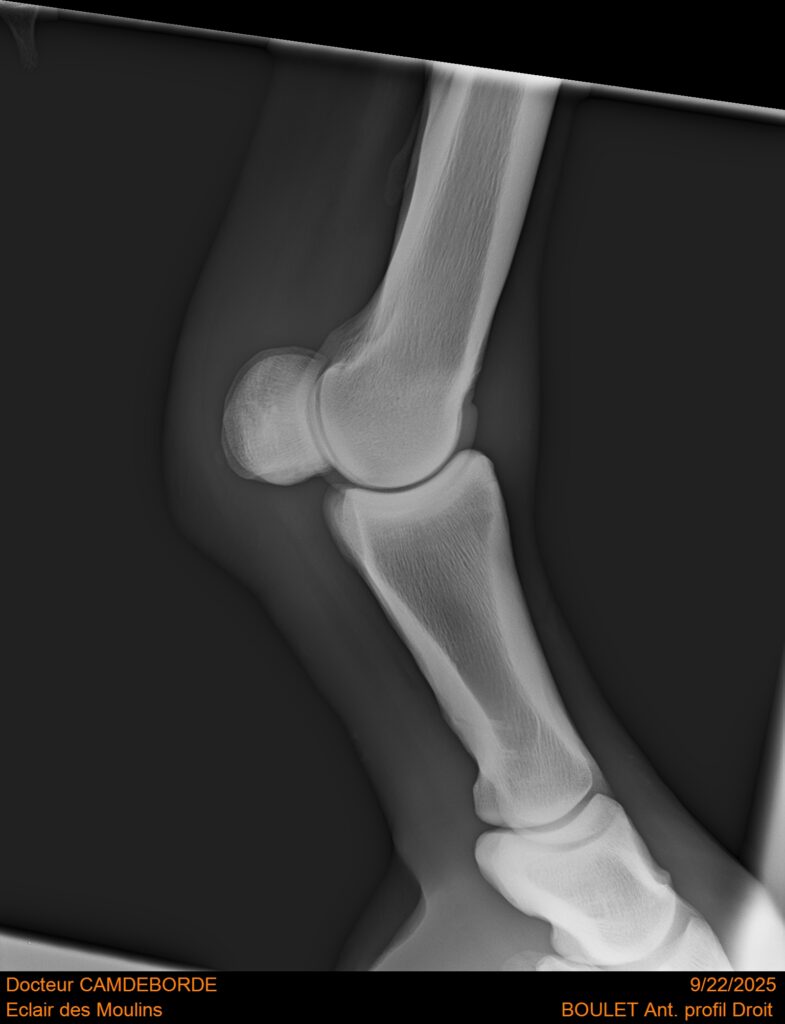

10 K ✨ TOP cheval pour épreuve Amateur ! ECLAIR DES MOULINS, selle Français de 11 ans. Classé sur 1m05. Idéal pour aller faire jusqu’à 110 voir 115, cheval pas usé (une vingtaines de parcours). Très gentil au quotidien, cheval de famille. Courageux et respectueux à l’obstacle. Bien dressé, change de pieds. Bilan pieds, boulets, jarrets, grassets et visite clinique effectuée cette semaine. il peut vivre au box comme au champs, cheval rustique. toise environ 1m60 porteur. Pour le compte de son propriétaire car manque de temps.

RADIOS ET CLINIQUE